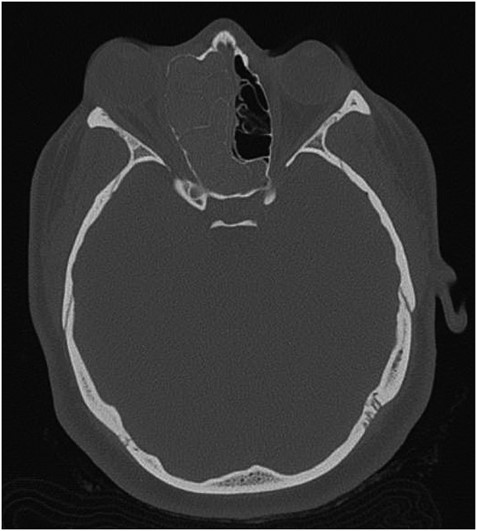

Axial CT view of the ethmoid labyrinth with the left side super imposed on the right side over the midline for comparison.

AFS is a known risk factor for development of nasal polyps [5, 6]. Incidences of AFS causing unilateral proptosis have also been described in the literature [7, 8]. The findings from the current CT, however, indicate a unique developmental process. When compared to the patient’s left side, the extent is easily seen (Fig. 3). In consideration of the preservation of the ethmoid architecture along with the patient’s age, it appears that due to the severity and duration of the polyposis and AFS, the ethmoidal labyrinth malformed while still in development. Contrastingly, in cases of several nasal polyposis, including those with ocular involvement, bone erosion and destruction are most frequently seen with respect to changes in bone anatomy [9]. Chronic remodeling of the ethmoid bone has been described in venous malformations [10], however, cases of nasal polyps leading to bone malformation are significantly underrepresented in the literature. CT imaging proved the most valuable diagnostic tool in examining the extent of the proptosis secondary to polyposis, as well as describing the changes in the ethmoid labyrinth structure. Surgical approach proved effective in reducing the patient’s symptoms, as well as confirming the etiology of the unilateral proptosis.